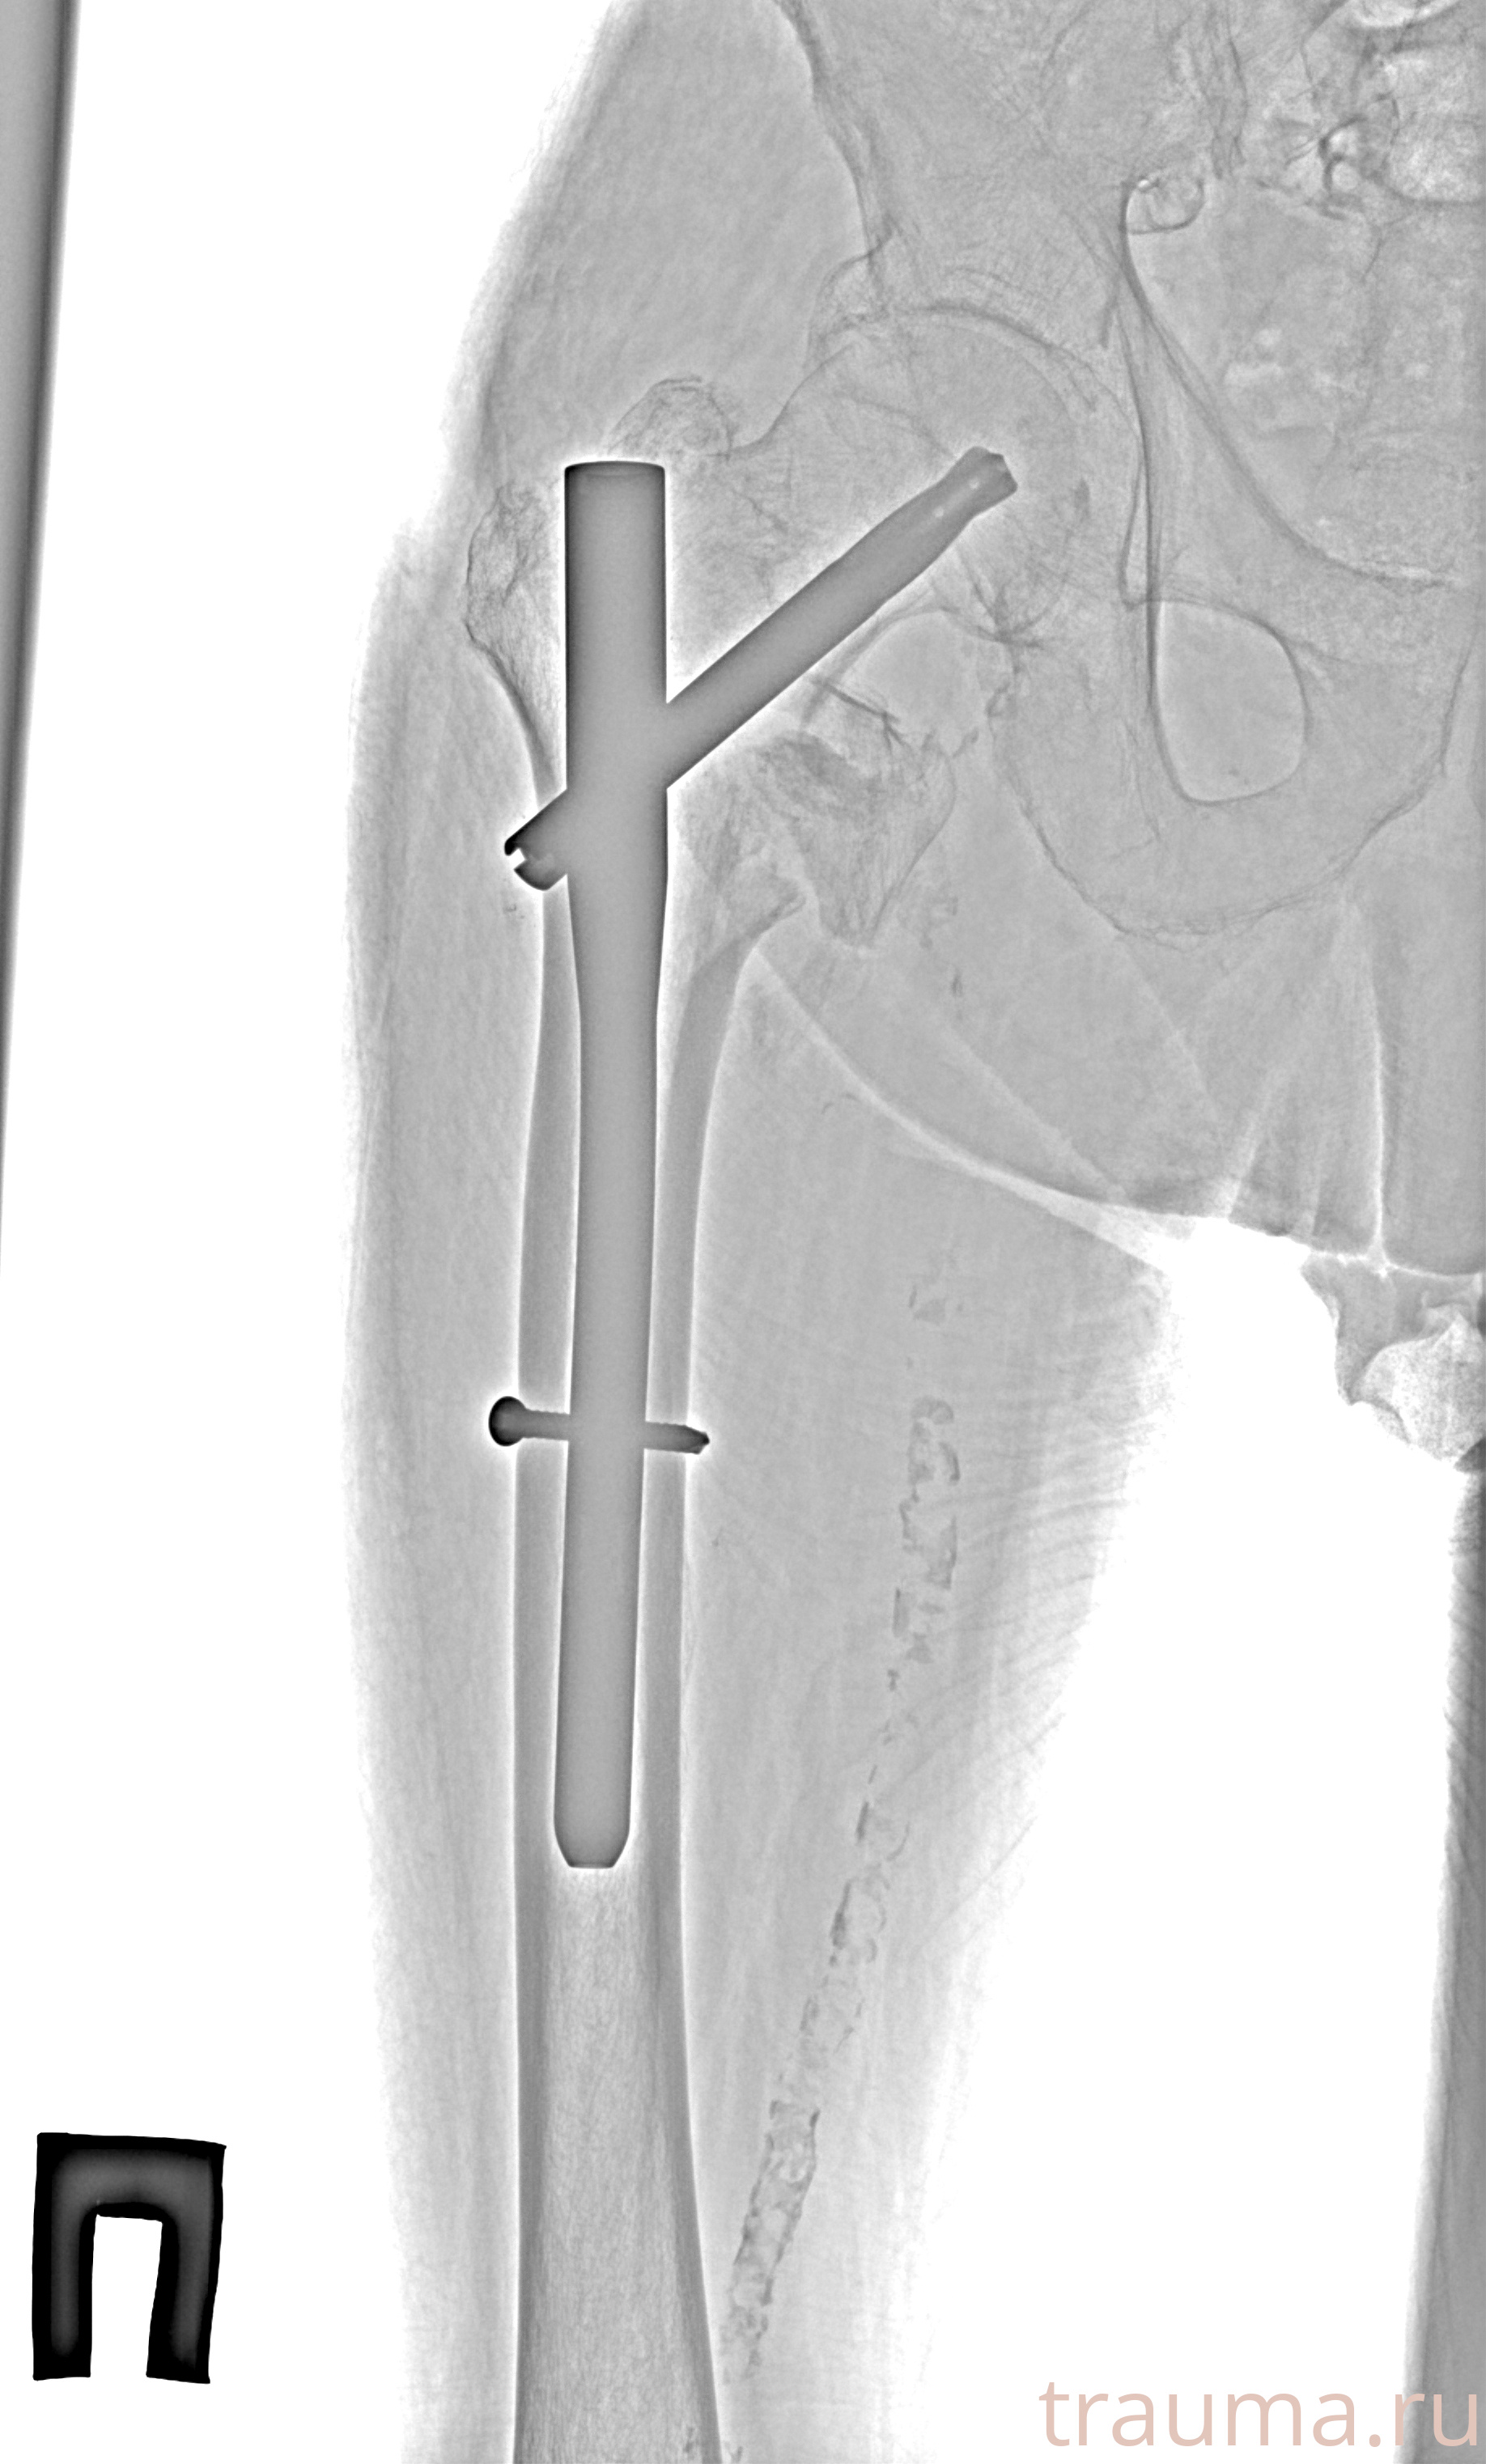

Рентгенограммы